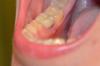

atom Опубликовано 25 апреля, 2013 Поделиться Опубликовано 25 апреля, 2013 (изменено) Здравствуйте, профи! У меня рядом с мертвым зубом (штифт+коронка) надувается пузырь (шарик) на десне с внутр стороны. Рядом с ним пломбированный зуб и между ними щель, где застревает еда.Впервые пузырь появился через 2,5 года после того как поставили коронку и пломбу. В тот раз у меня не было с собой зубной нити и поблизости негде было купить.Второй раз пузырь появился через 8 месяцев, в это время я была беременна. Зубной нитью пользовалась регулярно.После родов пузырь стал появляться очень часто, хотя я каждый день пользуюсь зубной нитью.Но только ночью. К утру он исчезает, но из него ничего не вытекает. И это не каждую ночь. Поэтому проблематично показать врачу.При надавливании не болит. Температуры не было.Вначале он был только остроконечный с белой серединкой, но иногда раздувается больше и принимает форму полусферы. Читала информацию про свищ и афтозный стоматит, но это не похоже ни на одно, ни на другое. Фотки, хоть и не очень резкие. надеюсь, что-то подскажут. Подскажите, пожалуйста, что это может быть и что с этим делать. Заранее благодарна. Изменено 25 апреля, 2013 пользователем atom Ссылка на комментарий